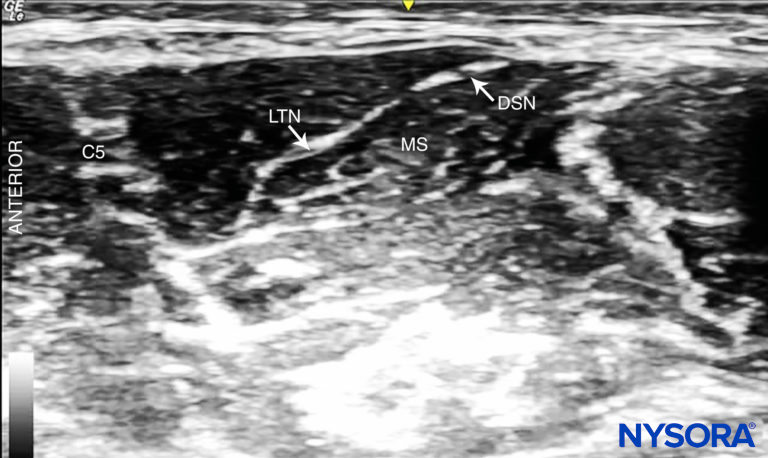

• The lateral-to-medial insertion is often chosen to prevent injury to the phrenic nerve, which is typically located anteriorly to the anterior scalene, although one should be aware that the dorsal scapular nerve and the long thoracic nerve usually course through the middle scalene and could potentially be injured as well (Figure 9).

FIGURE 9. Dorsal scapular nerve (DSN) and long thoracic nerve (LTN) visible in the middle scalene muscle (MS).